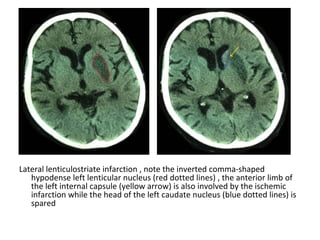

Lateral lenticulostriate infarction , note the inverted comma-shaped

hypodense left lenticular nucleus (red dotted lines) , the anterior limb of

the left internal capsule (yellow arrow) is also involved by the ischemic

infarction while the head of the left caudate nucleus (blue dotted lines) is

spared